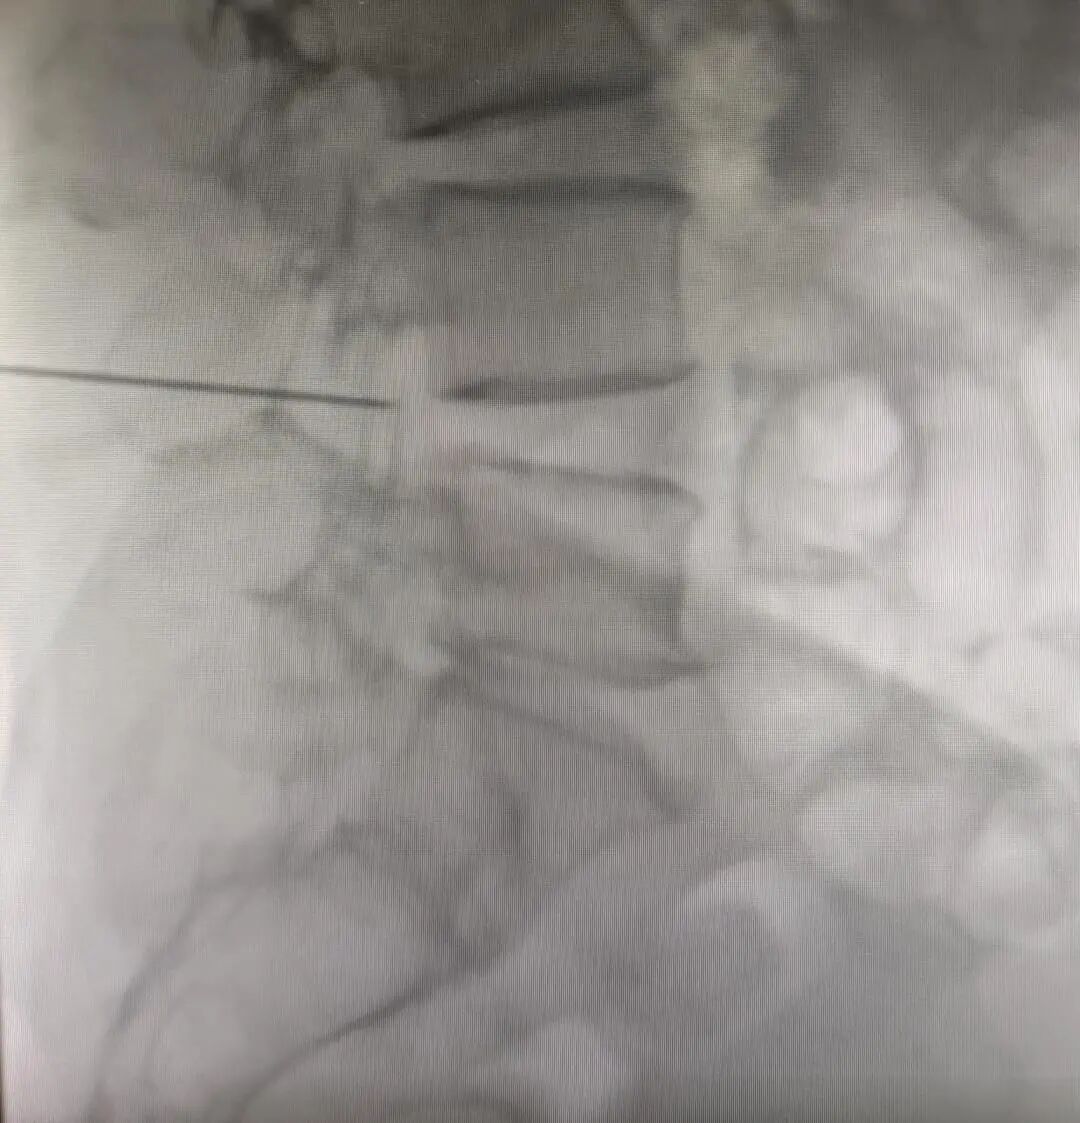

治疗在介入诊疗中心的飞利浦FD20透视引导下进行,肉眼不可及的人体内部解剖结构——椎体和周围软组织的形态和结构等,都在X线的引导下一览无余,方便医生更准确看清椎间孔位置。

医生手中操纵的穿刺针也能更加精准地从皮肤进入到达脊神经根部位。在设备助力下,手术医生赖显金一针到位,在神经干、丛、脊神经根旁靶向注入阻滞药物,使所支配的区域产生麻醉作用,起到镇痛效果。